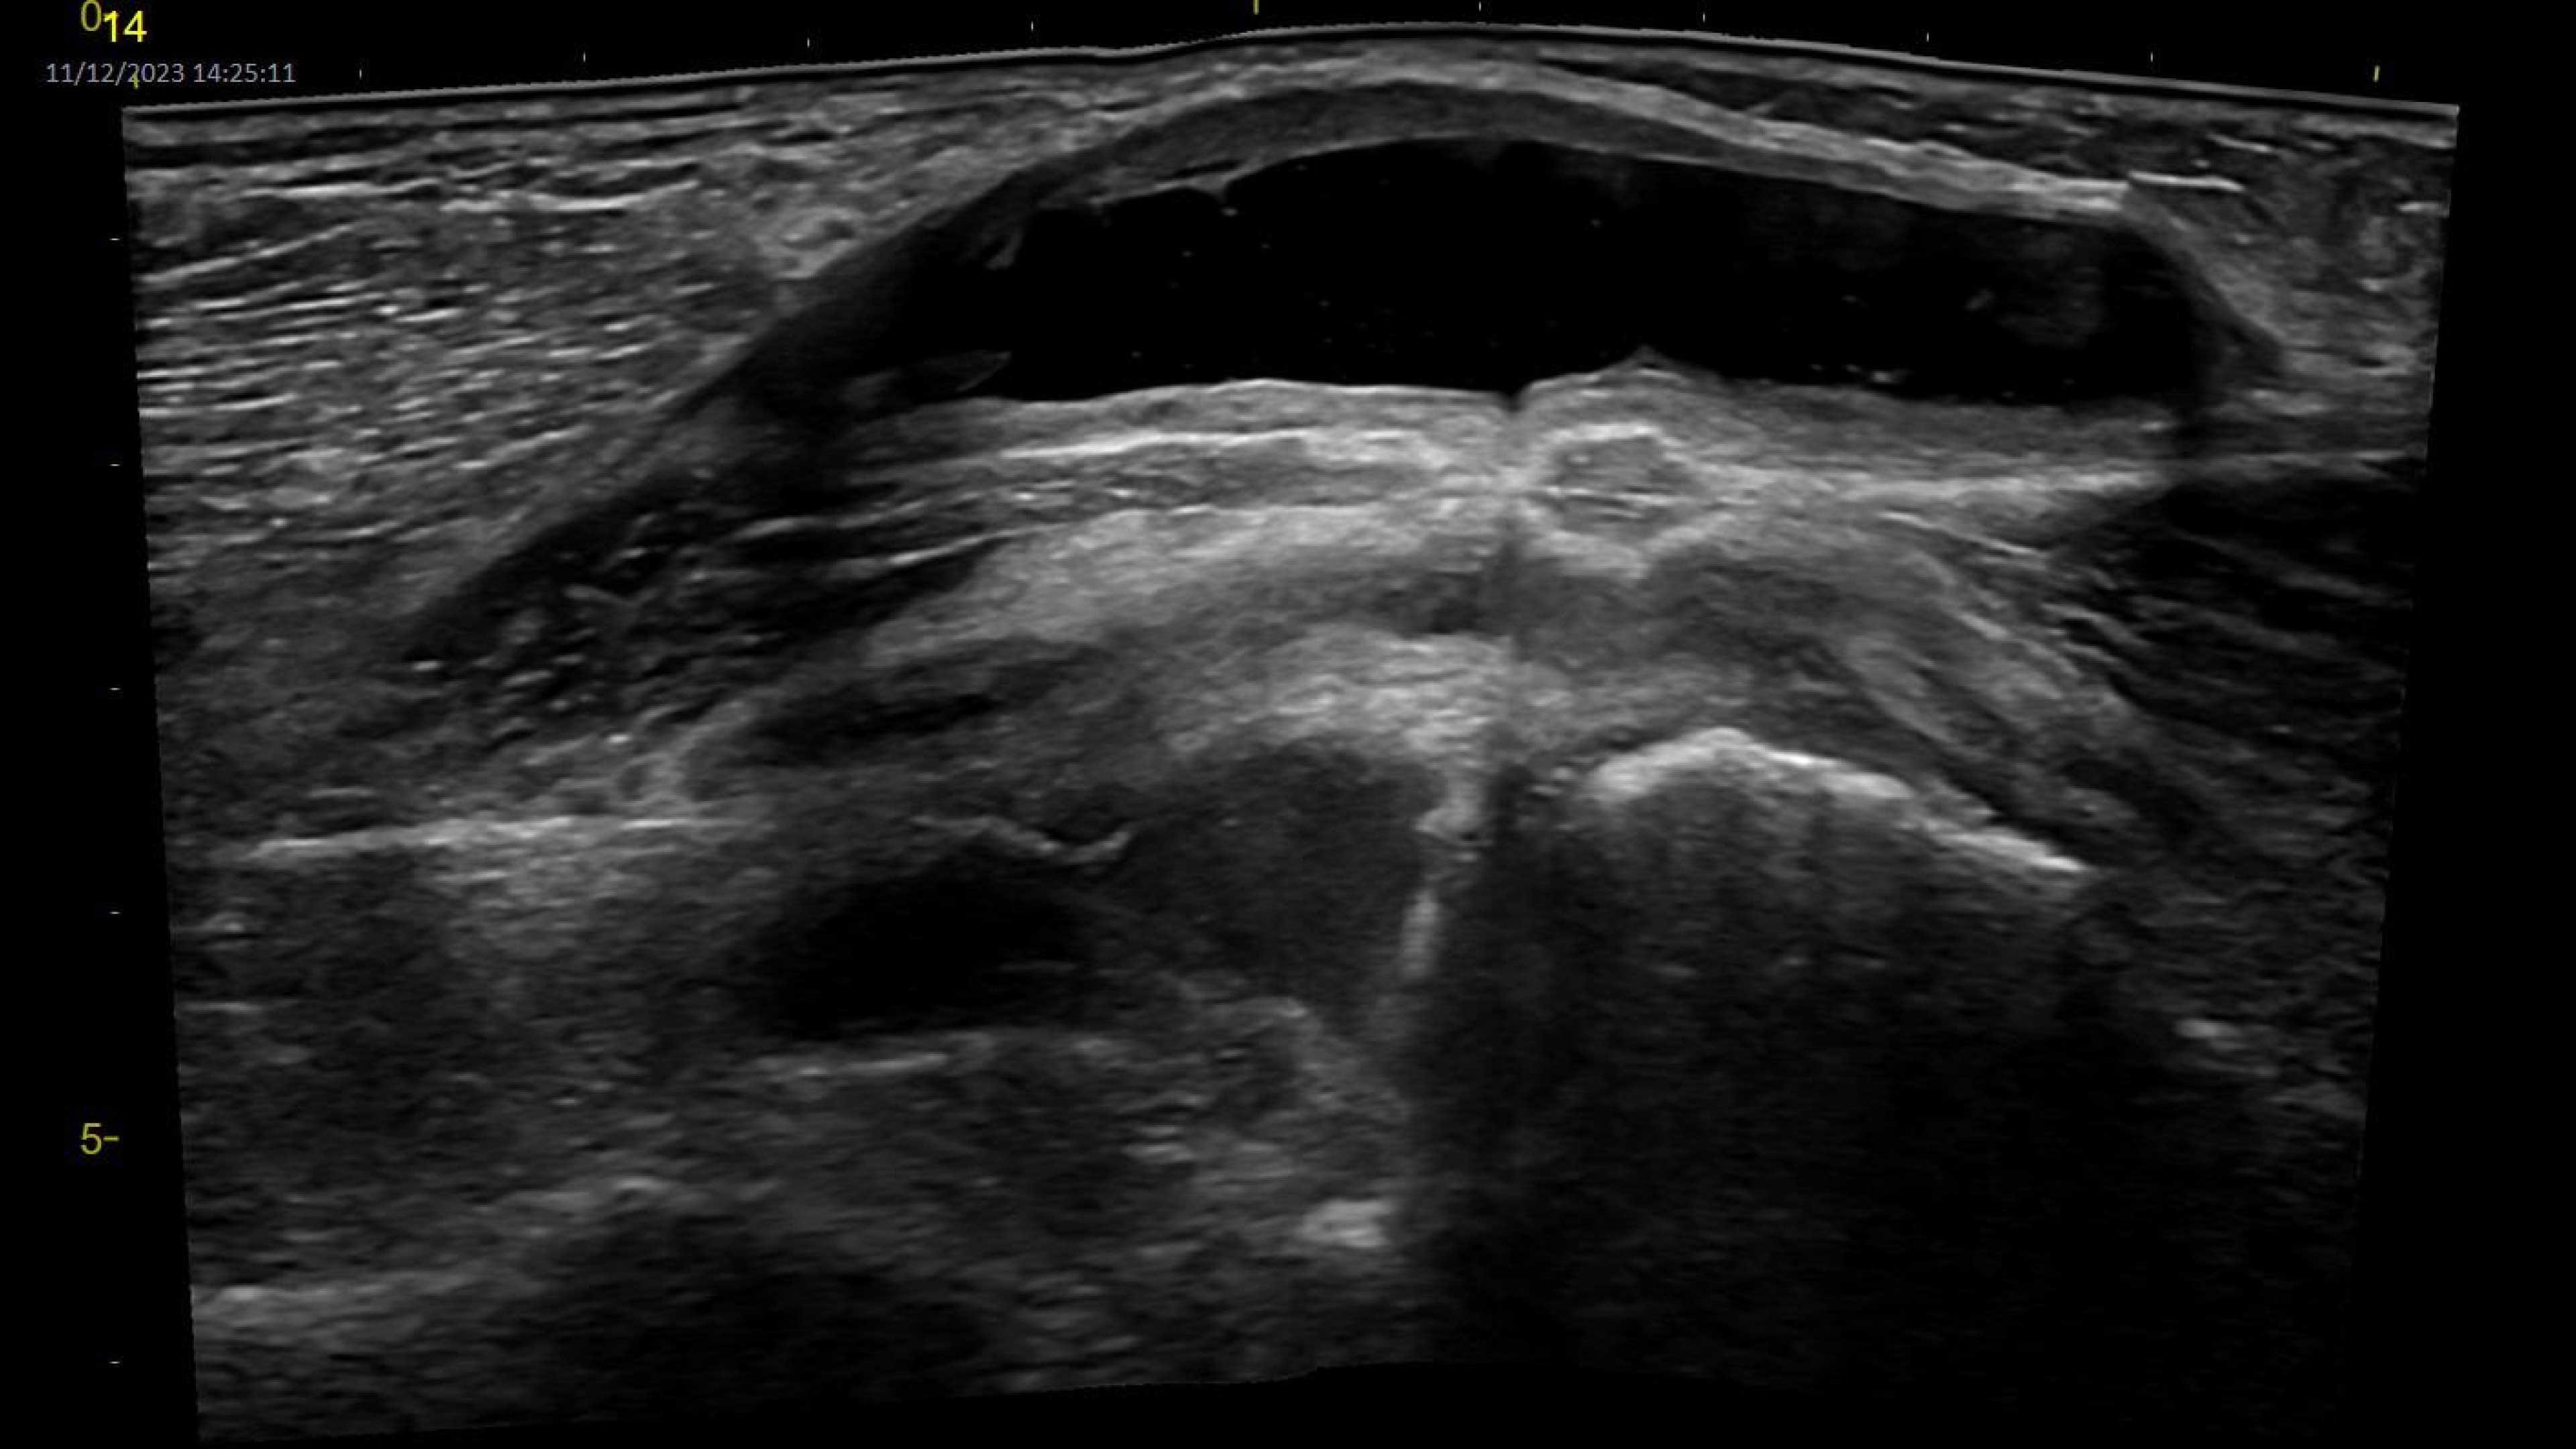

Wireless probe integration

Sync up and go - without wires you’re not tethered to a system or a space

Small yet powerful

Flexible, wireless dual-probes deliver clear images and Venue family software

Easy to clean

Smooth and seamless surfaces support infection control efforts